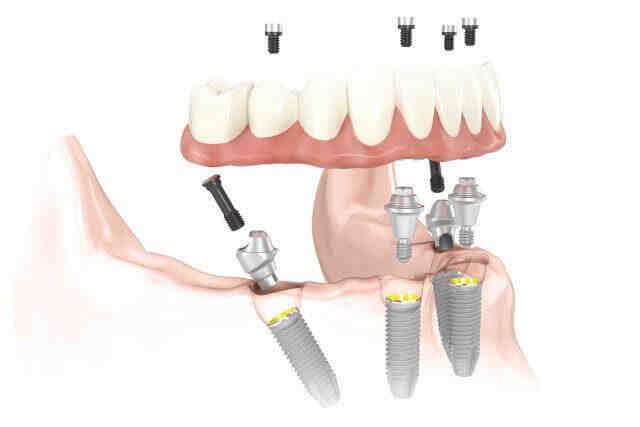

How much are all on four dental implants?

The Cost of an All Dental Implant 4 You should be prepared to spend about $ 25,000 per arch on this solution. It can be as little as $ 12,000 or as high as $ 50,000. The higher mark will come from additional factors that go into the procedure such as bone grafting to strengthen the jawbone.

Can 1 implant replace 2 teeth?

One Dental Implant One dental implant can also be used to replace two adjacent teeth. Once the implant is attached to the body, your dentist will replace it with a two-unit replacement. One unit will be a crown, and the other unit will be pontic (artificial tooth attached to the crown).